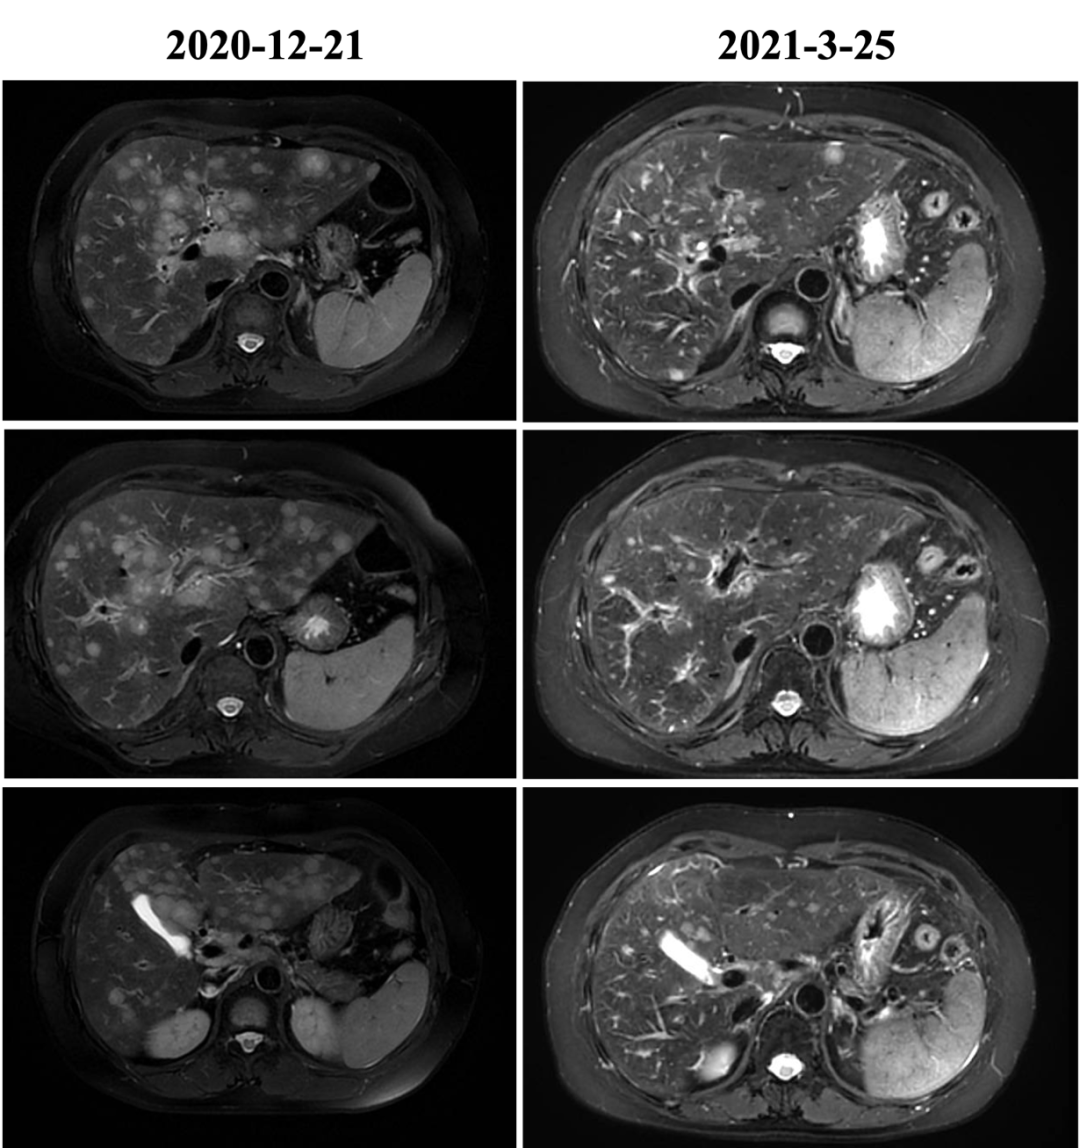

▌六线治疗:

2020-12-22始行吉西他滨+曲妥珠单抗(汉曲优)+帕妥珠单抗治疗,具体:吉西他滨1g/m2 1.6g d1、1.8g d8;曲妥珠单抗首次 8mg/kg 520mg,以后6mg/kg 390mg,帕妥珠单抗首次840mg,以后420mg,d1,Q21d;自第10周期开始双靶维持治疗。2021-03-25复查:肝内多发转移较前减少、缩小(较大24x20mm→12x11mm),肝门区及门腔间隙淋巴结缩小(28*18mm→12*7mm),左侧肋骨转移减轻),最佳评效PR。2021-12-15头MRI示可疑脑膜转移,评效PD,PFS为12月。不良反应:手足麻木2度,肝功损伤2度。

图7 六线治疗